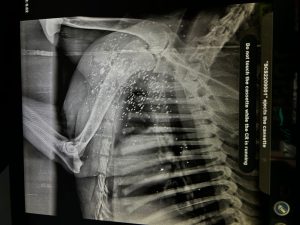

Животное находилось при смерти, когда его доставили в клинику в Кутаиси. Чтобы извлечь дробь, потребовалась сложная операция.